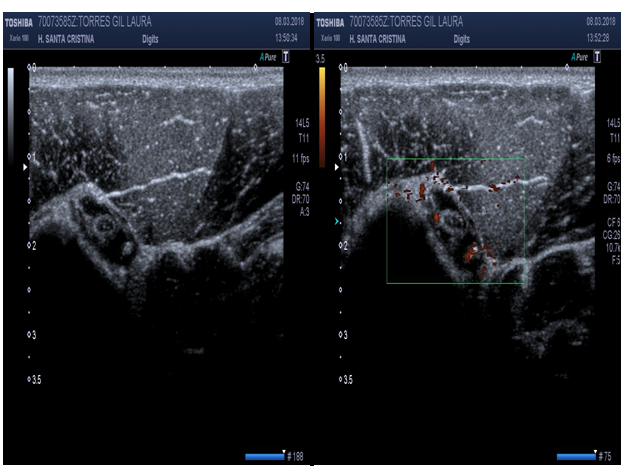

Infraspinatus tendon (long axis) (Figure 9)

Patient position: Patient is seated, back toward the examiner, arm on contralateral shoulder (“military position”).

Probe position: Probe placed longitudinal to posterior glenohumeral joint.

Scan of structures: Scanning superior above scapular spine is supraspinatus tendon. Below the spine, infraspinatus and teres minor muscles can be seen. Suprascapular notch may be visualized, better if color Doppler is used.17,18

Abnormal findings: Suprascapular notch may have a cyst present.17,18

Rotator cuff interval (subscapularis, biceps tendon and supraspinatus) (Figure 10)

Patient position: Patient facing direction of shoulder been studied, 90º to the examiner with hand on back pocket and elbow tucked in (“Marilyn Monroe position”).

Probe position: Probe on coronal position.

Scan of structures: Axial over bicipital grove, sweep probe proximally to the acromion to view the supraspinatus, distally down to view the infraspinatus.17,18

Figure 9 Sonoanatomy of the infraspinatus tendon (long axis).

Figure 10 Sonoanatomy of rotator cuff interval (Subscapularis, biceps tendon, supraspinatus tendon).